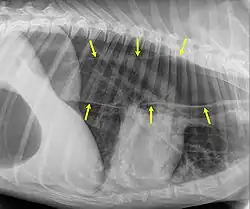

Megaesophagus, also known as esophageal dilatation, is a disorder of the esophagus in humans and other mammals, whereby the esophagus becomes abnormally enlarged. Megaesophagus may be caused by any disease which causes the muscles of the esophagus to fail to properly propel food and liquid from the mouth into the stomach (that is, a failure of peristalsis). Food can become lodged in the flaccid esophagus, where it may decay, be regurgitated, or be inhaled into the lungs (leading to aspiration pneumonia).[1]